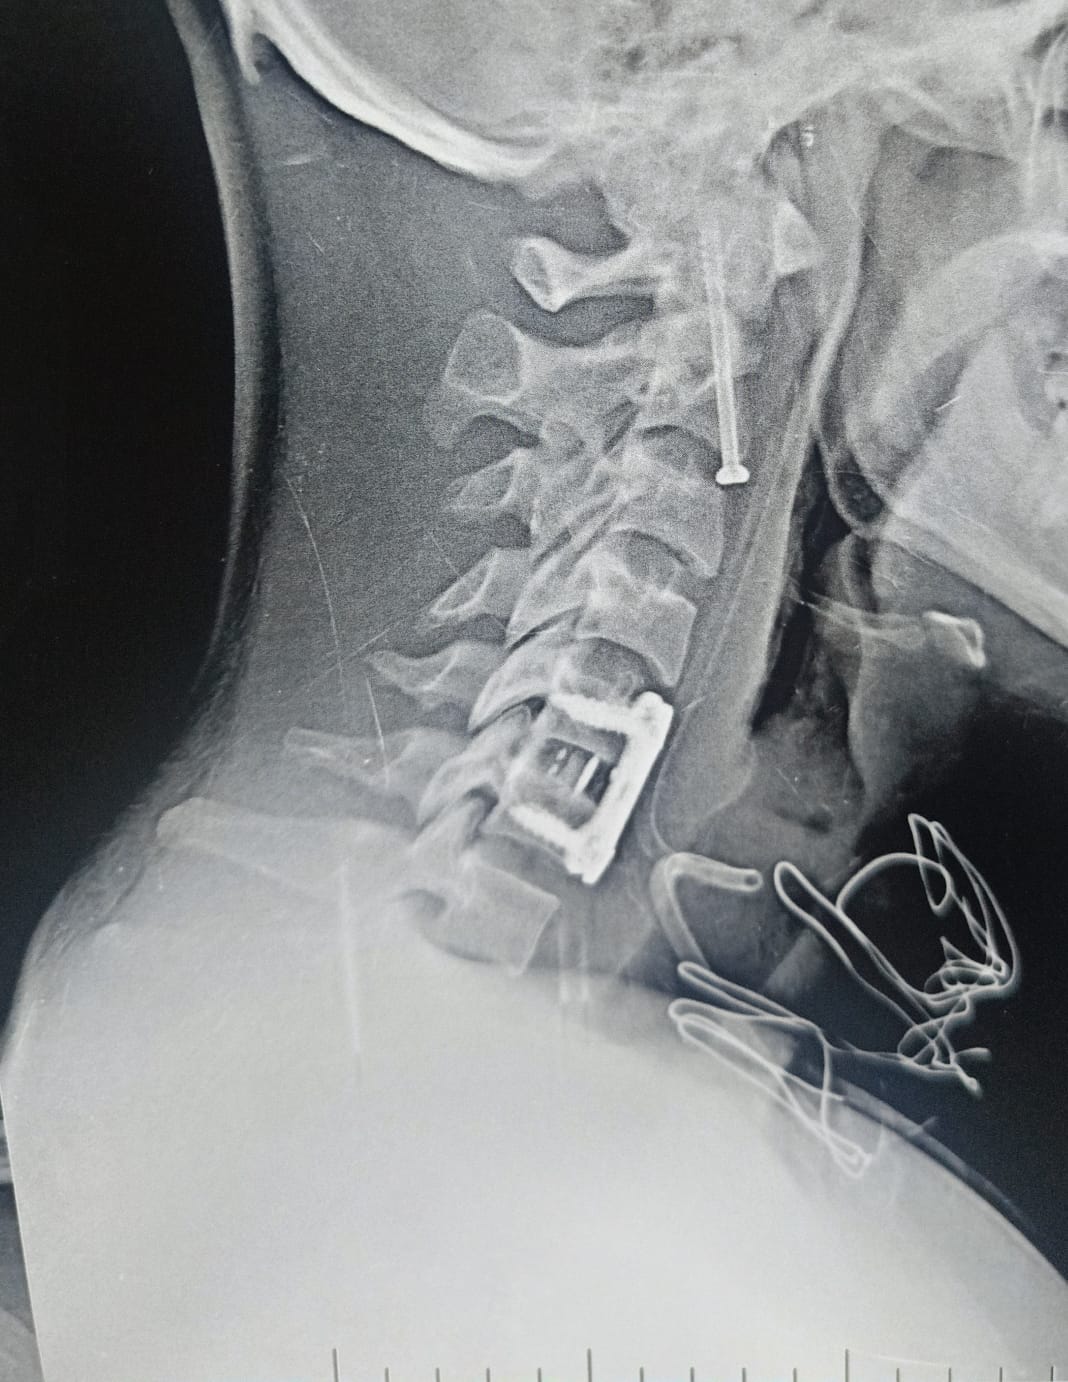

أشعة أجريب للمريض

وكان قسم الاستقبال والطوارئ بمستشفيات جامعة بنها قد استقبل المريض عقب سقوطه من علو، وبالفحص والأشعة تبين إصابته بكسر في الفقرة العنقية الثانية، وهي من أكثر المناطق خطورة لقربها من جذع المخ المسؤول عن الوظائف الحيوية، إضافة إلى وجود تزحزح فقاري بين الفقرتين الخامسة والسادسة.

وأُجريت الجراحة تحت إشراف وتوجيه الدكتور إسلام أبو الفتوح رئيس قسم جراحة المخ والأعصاب، والدكتور إيهاب سعيد رئيس قسم التخدير، حيث تمكن الفريق الطبي من تثبيت كسر الفقرة العنقية الثانية بدقة عالية، إلى جانب تثبيت التزحزح الفقاري بين الفقرتين الخامسة والسادسة باستخدام شريحة ومسامير وقفص عنقي.